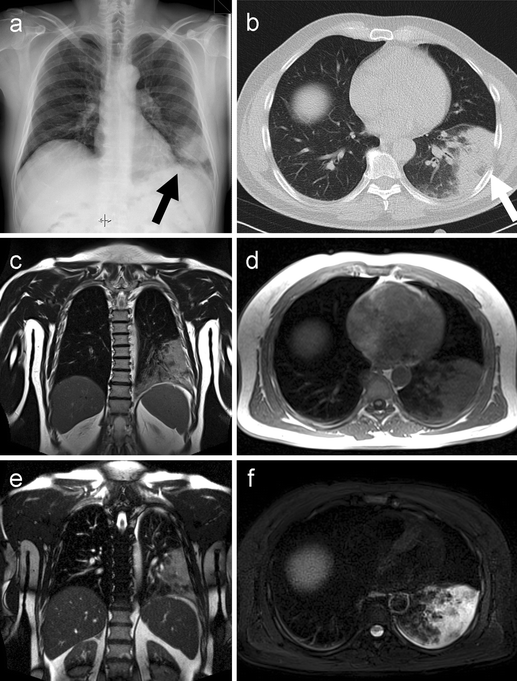

MRI study of lung cancer in a 66year old patient with coal worker’s What Can Mri Detect In Lungs Advances in lung magnetic resonance imaging. A special form of mri called magnetic resonance angiography (mra) is helpful to assess the vessels of the chest cavity (arteries and veins). Mri/mra of the chest can also be used to diagnose aortic dissection. Mri is more sensitive and can. Mra can also demonstrate an abnormal ballooning out of the wall of an. What Can Mri Detect In Lungs.

From www.svuhradiology.ie

Lung cancer CXR Radiology at St. Vincent's University Hospital What Can Mri Detect In Lungs A special form of mri called magnetic resonance angiography (mra) is helpful to assess the vessels of the chest cavity (arteries and veins). [8,9] the value of mri in patients with pulmonary nodules have already il. Mri/mra of the chest can also be used to diagnose aortic dissection. The central challenge of pulmonary mri comes from the low proton. Mra. What Can Mri Detect In Lungs.